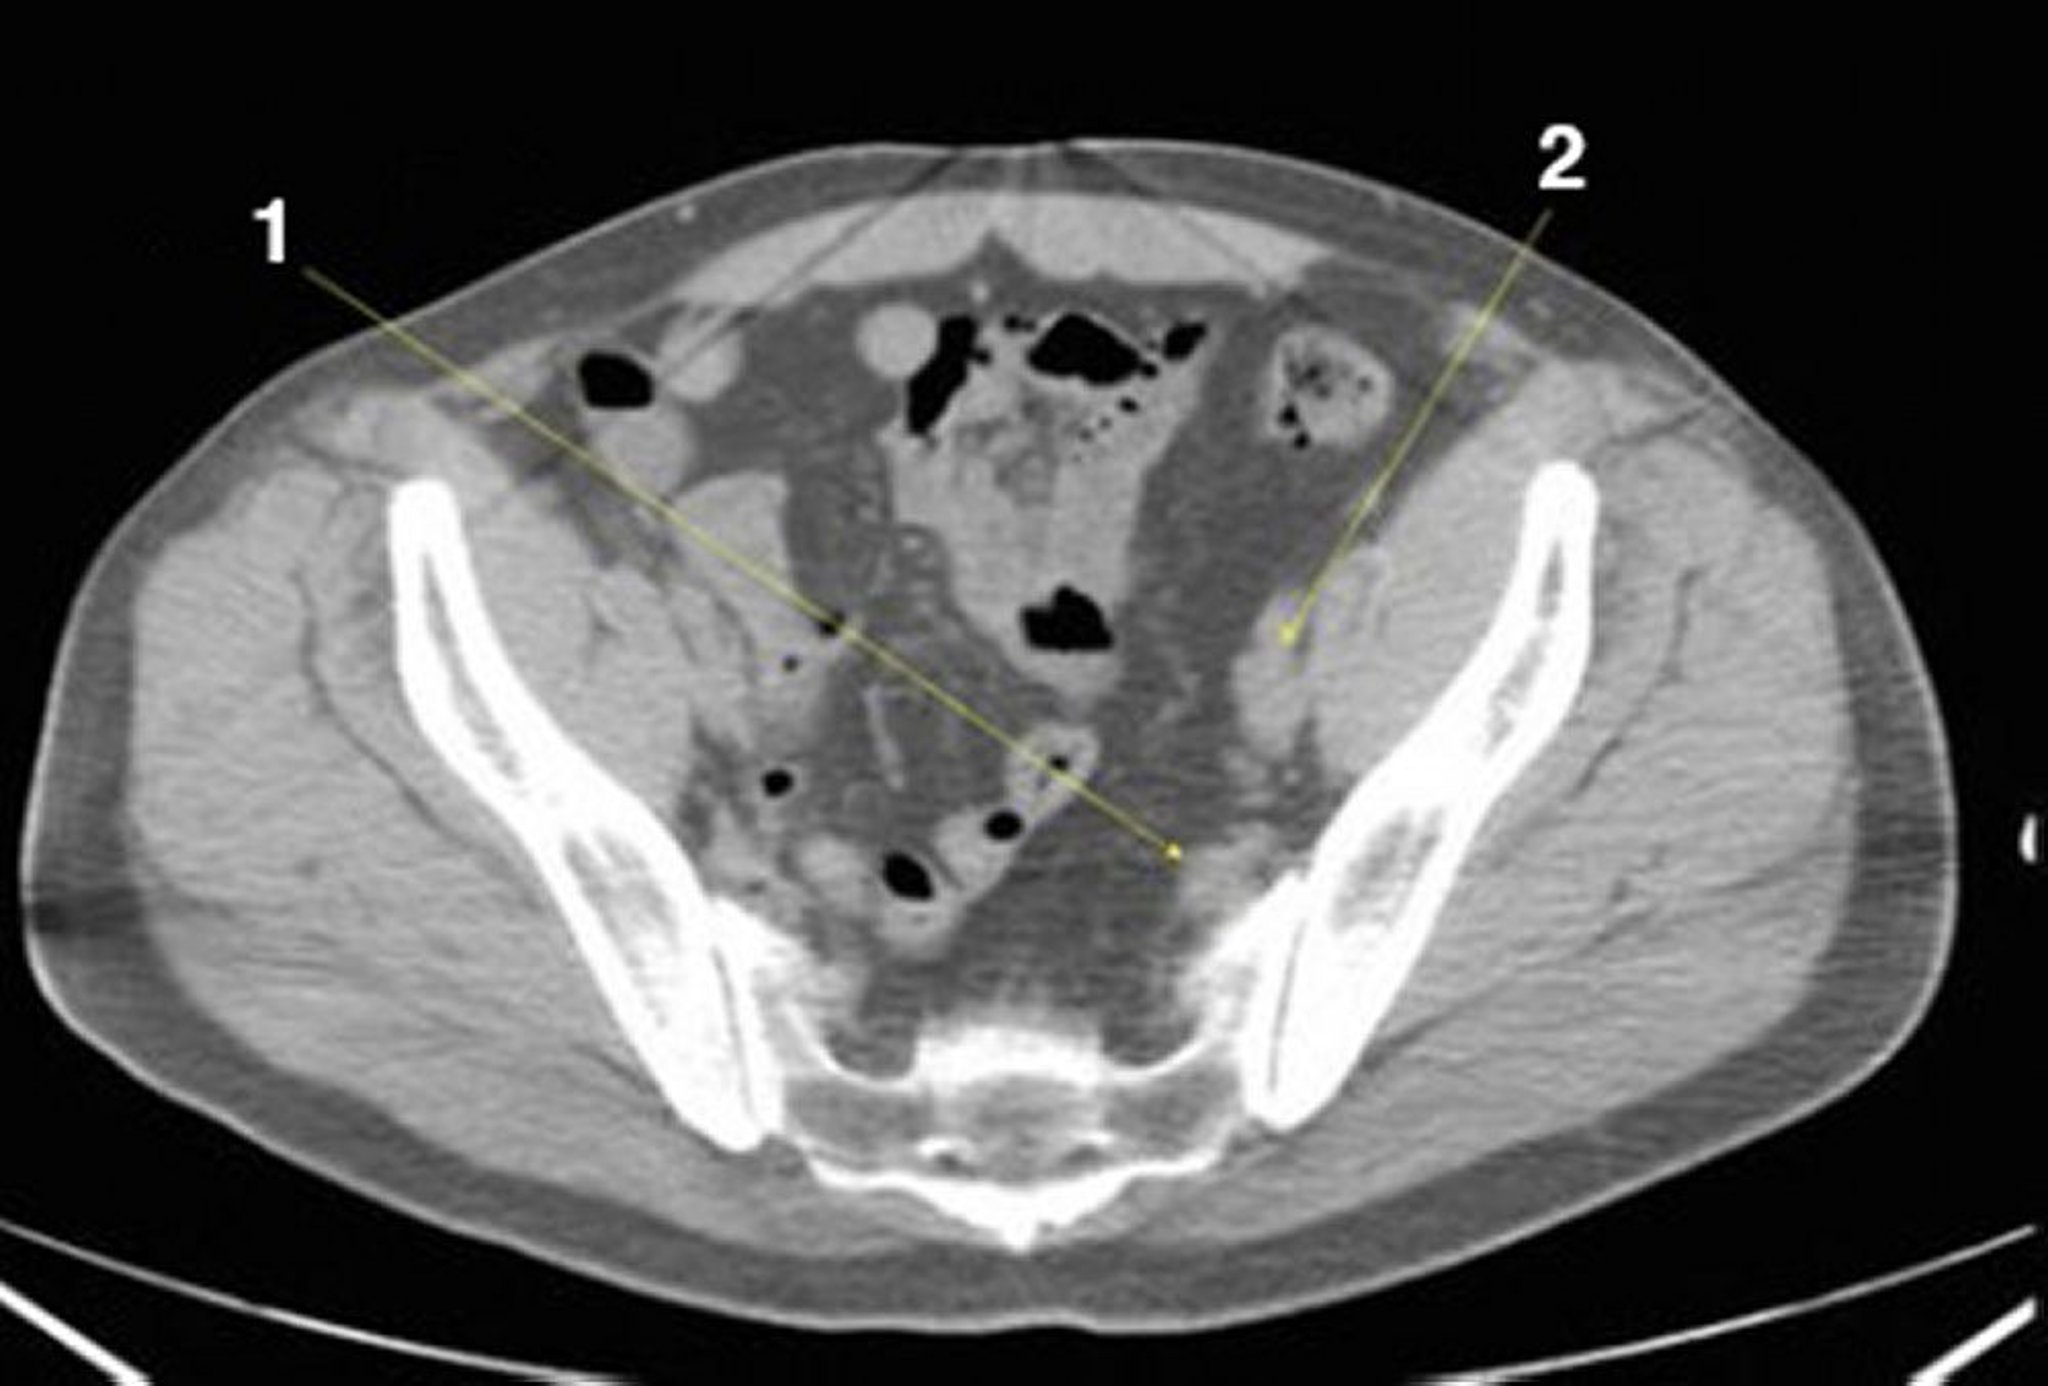

Noncontrast CT Scan of the Abdomen and Pelvis Showing Normal Anatomy (Slide 24)

1 = internal iliac vessels; 2 = external iliac vessels.